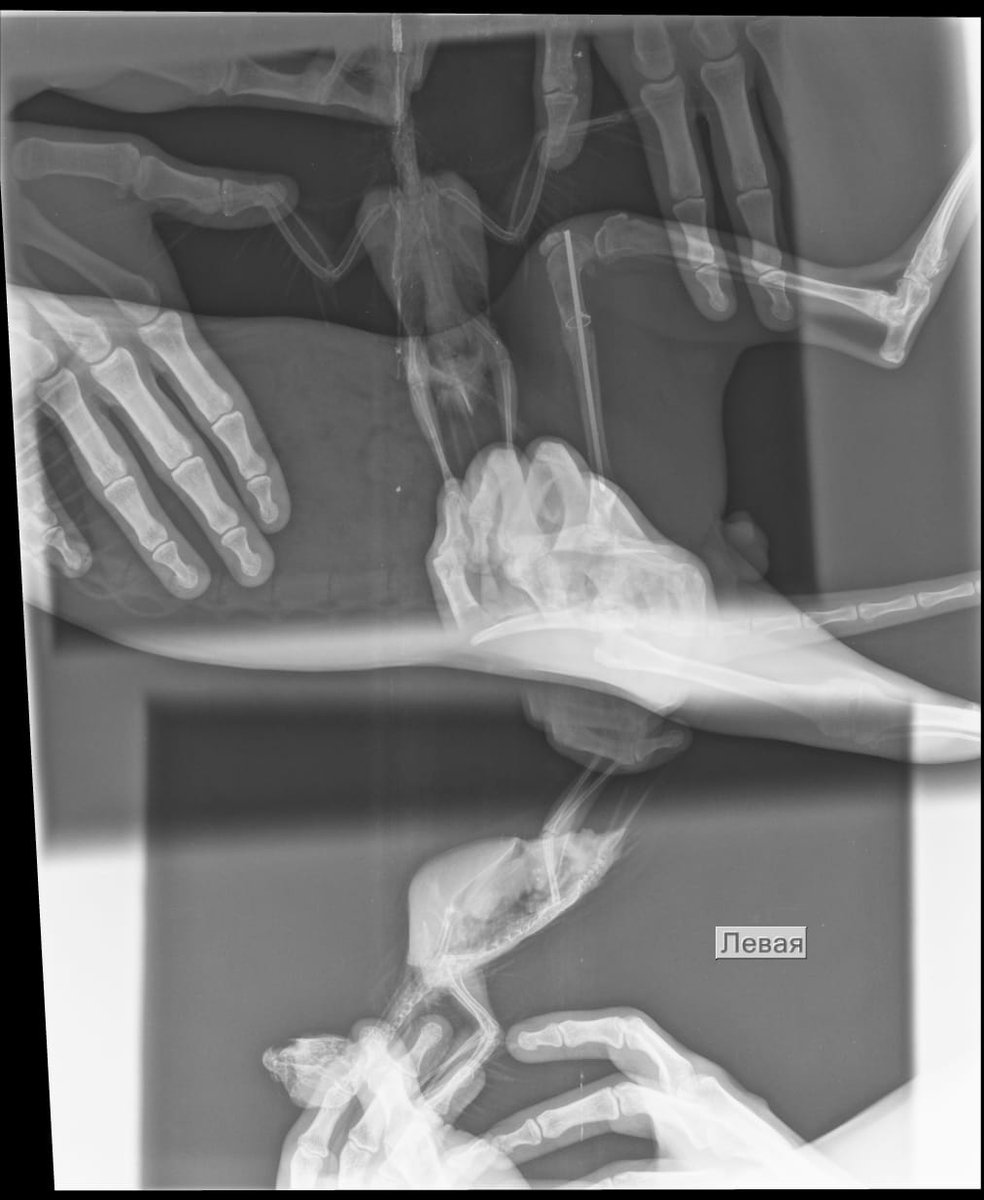

начали сдавать анализы дальше. и сделали рентген. По рентгену - воспаление воздухоносных мешков, пневмония, увеличение границ печени (наверное, я перелечил ее).

IMG-20201020-WA0006.jpg

У птицы в крови завышена щелочная фосфатаза. на рентгене - пневмония и воспаление воздухоносных мешков. Птица прикрывает глаза, при этом издает звуки клювом (или из носоглотки они идут), видно, что чешет клювом в в этот момент. Что это? Помогите пожалуйста. Птица более более полугода, с момента покупки.